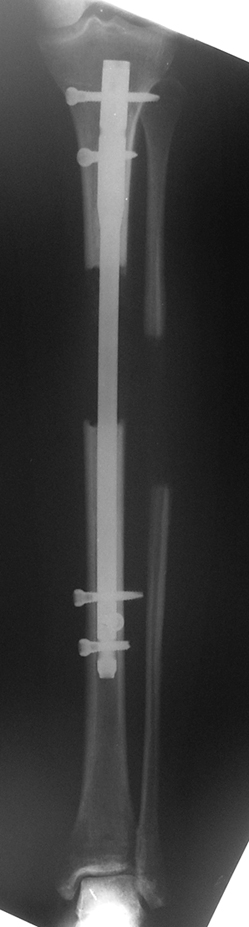

Installment of the intramedullary nail and osteotomy:

The patient lies is supine position at a traction table and legs are crossed with the uninvolved leg at the bottom. The medullary cavity is penetrated through piriform fossa using the standard method, and medulla is reamed 1.5 mm thicker than the nail to be used, over a guidewire. Proximal femur is reamed more, because the intramedullary nail is thicker proximally. The osteotomy site is planned at the X-Rays. It is important that at least 8 cm. of nail remains distal to the osteotomy site after the completion of the lengthening procedure. Percutaneous corticotomy is performed. The guide wire is advanced distally in order to measure the length of the nail. An intramedullary nail of apropriate length is placed. In the end, the nail is interlocked proximally, a suction drain is placed and the fist step of the operation is completed.

2. Step:

The application of the external fixator: Three Schanz screws are placed distally and three screws are placed proximally. At least 1 mm of distance shall remain between the screws and the nail.

In selected cases, we prefer to use a combination of a unilateral dynamic axial fixator and an interlocked intramedullary nail, in order to protect the length and alignment after the completion of the lengthening procedure. As a prerequisite for this technique, the narowest diameter of the medullary cavity shall be wider than 7 mm and the length of the nail segment distal to the osteotomy site shall be at least 8 cm. after the completion of the lengthening procedure.The intramedullary nail neutralizes shear and bending forces on femur during lengthening, shortens external fixation time, and protects newly formed bone against fractures. In our series, subtrochanteric osteotomy was performed in one case. No varus angulation occured despite the intramedullary nail.